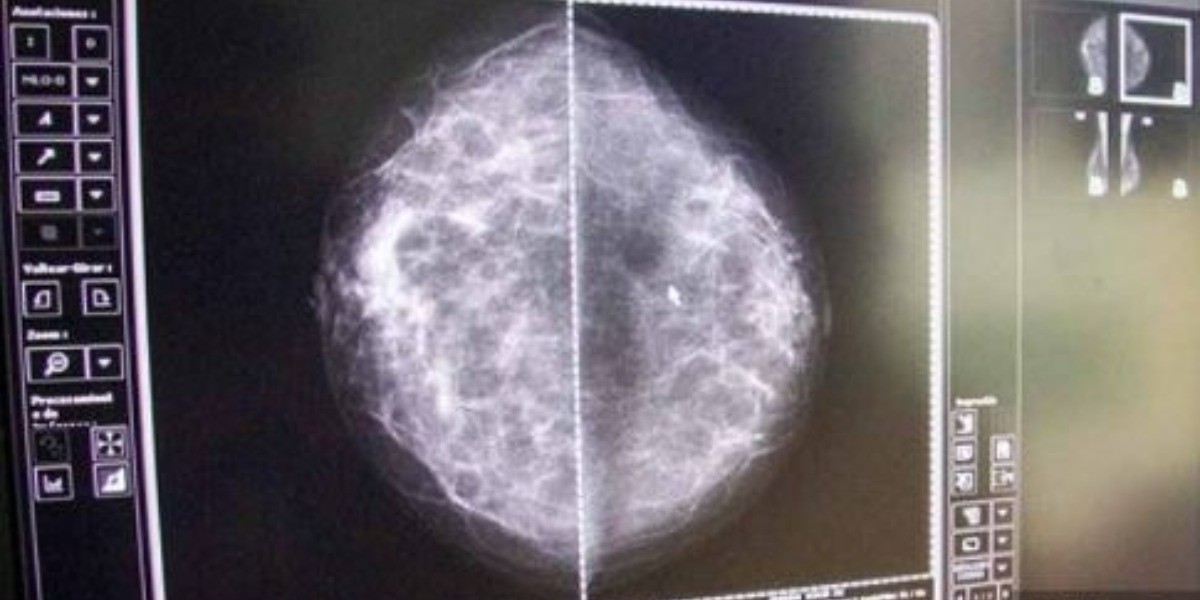

Por otro lado, la mastografía se realiza toda mujer que se encuentra en el grupo de edad de 40 a 59 años, si se trata de un estudio diagnóstico y de 50 a 69 años (mujeres asintomáticas).

La mastografía es una herramienta que permite diagnosticar de manera temprana y oportuna la enfermedad, siempre y cuando se cuente con controles de calidad, tanto en equipos (mastógrafos) como en la toma del estudio y la lectura de este.